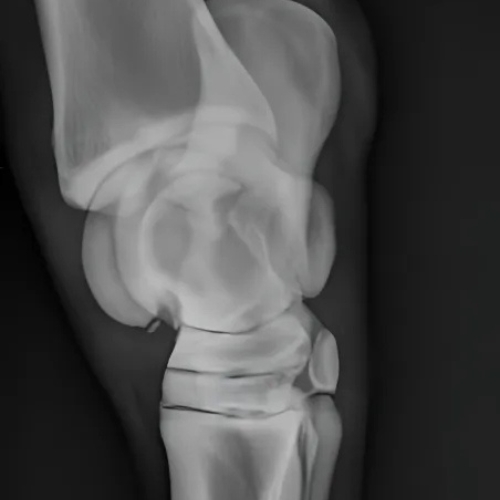

Digital imaging has transformed equine ambulatory care by enabling immediate access to high-quality diagnostic images. This advanced technology is especially critical for injuries that may require surgical referral, where time is often of the essence. Images can be shared electronically with specialists for additional evaluation, facilitating quicker and more informed decisions. Additionally, stall-side viewing supports real-time collaboration with farriers, particularly for complex podiatry cases like those involving laminitis or founder.

Equine digital imaging offers numerous advantages for both veterinarians and horse owners. One of the most significant is its ability to detect conditions at an early stage. Whether identifying a hairline fracture, joint abnormality, or a developmental concern, early diagnosis can lead to more effective treatment strategies and quicker recovery for the horse.

This technology also plays a vital role in formulating treatment plans. It helps determine the severity of an issue and guides veterinarians in choosing the most appropriate course of action—whether that’s medical management, rest, or surgery. Moreover, digital imaging is an essential tool in pre-purchase evaluations, offering buyers confidence and peace of mind when assessing a horse’s overall health.